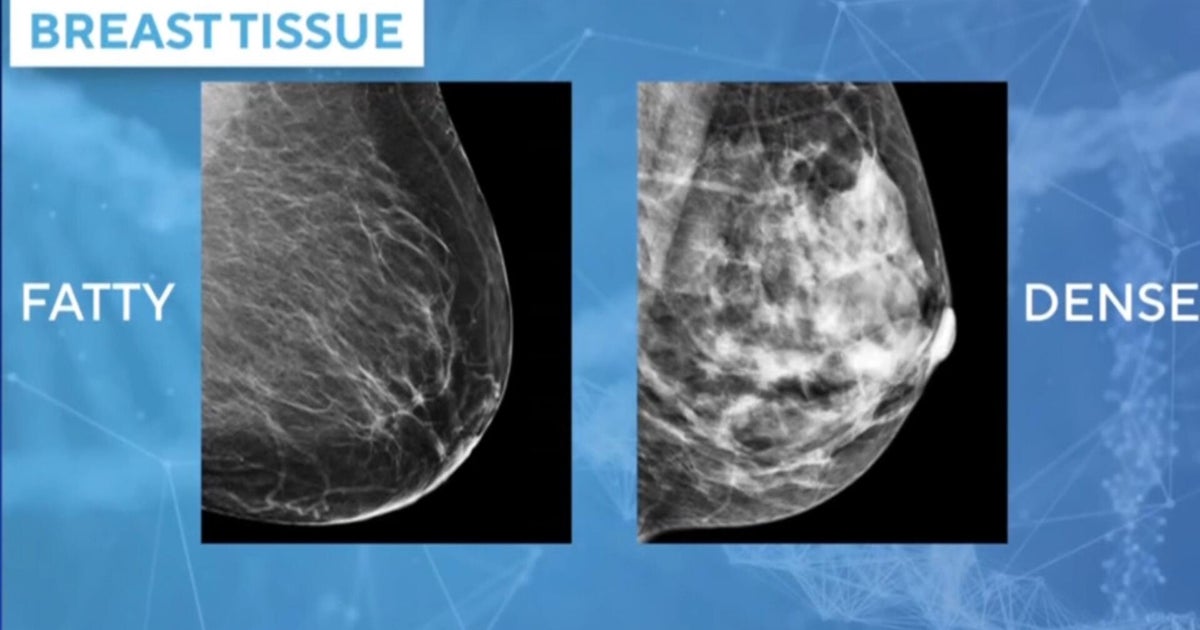

Breast cancer is the second-leading cause of cancer deaths in women. About one in eight women will be diagnosed with the disease in their lifetimes. To combat that, some doctors are using AI as a tool to help them not only detect breast cancer, but also predict a woman’s risk factors. Dr. Connie Lehman, founder of Clarity, joins CBS News to discuss the first FDA-authorized AI platform used to predict a woman’s 5-year risk of developing breast cancer.